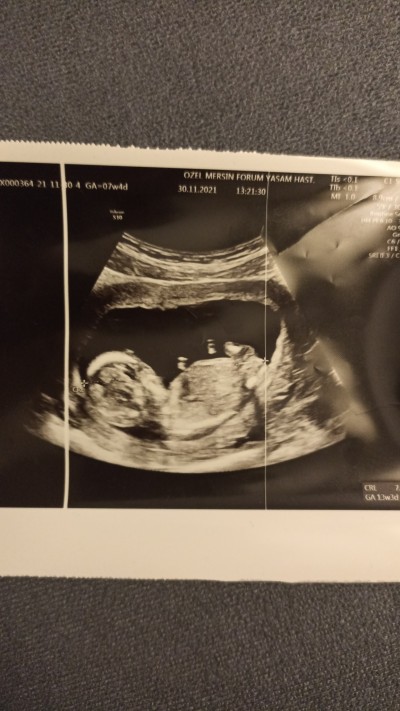

Doktor cinsiyeti söylemedi bacak arsina bakarmisiniz

image

Gebelik haftası 13

Çıkıntı görünmüyor sanki

Kemik yapısı kızı anımsatıyor